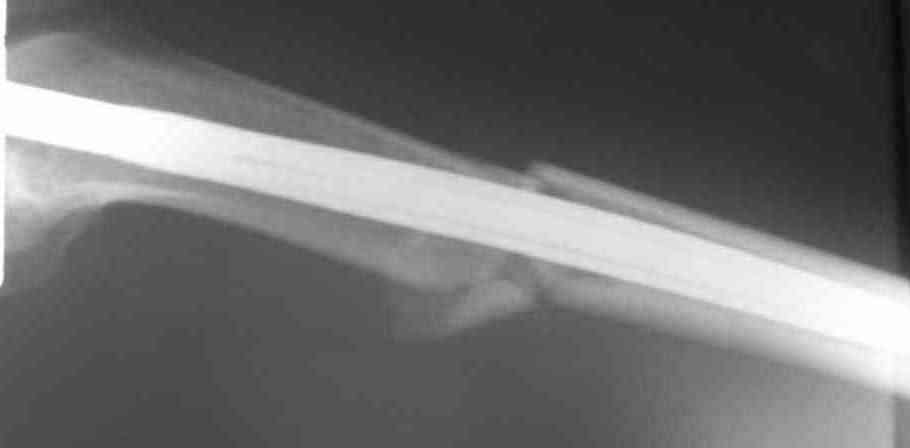

Дорогой Александр. Имею скромный опыт использования системы Fixion при переломах плеча, бедра и тибии. Всего 18 наблюдений с сентября 2006 г. Результаты отличные. Гвоздь индивидуален для каждого медуллярного канала. Легко имплантируется как в узкий, так и в деформированный канал. Это позволяет применять метод интрамедулярного остеосинтеза без ненужных потерь времени операции, флюороскопии и реально снижает крвопотерю и операционный риск. Удаление происходит без проблем. Особенно интересны больные с ипсилатеральными переломами бедра и голени.

> Особенно интересны больные с ипсилатеральными переломами бедра и голени.

Да, спасибо за интересные иллюстрации. Получилось очень симпатично. На большеберцовой кости непременно надо было винты? Там же был торцовый упор, перелом в средней трети?